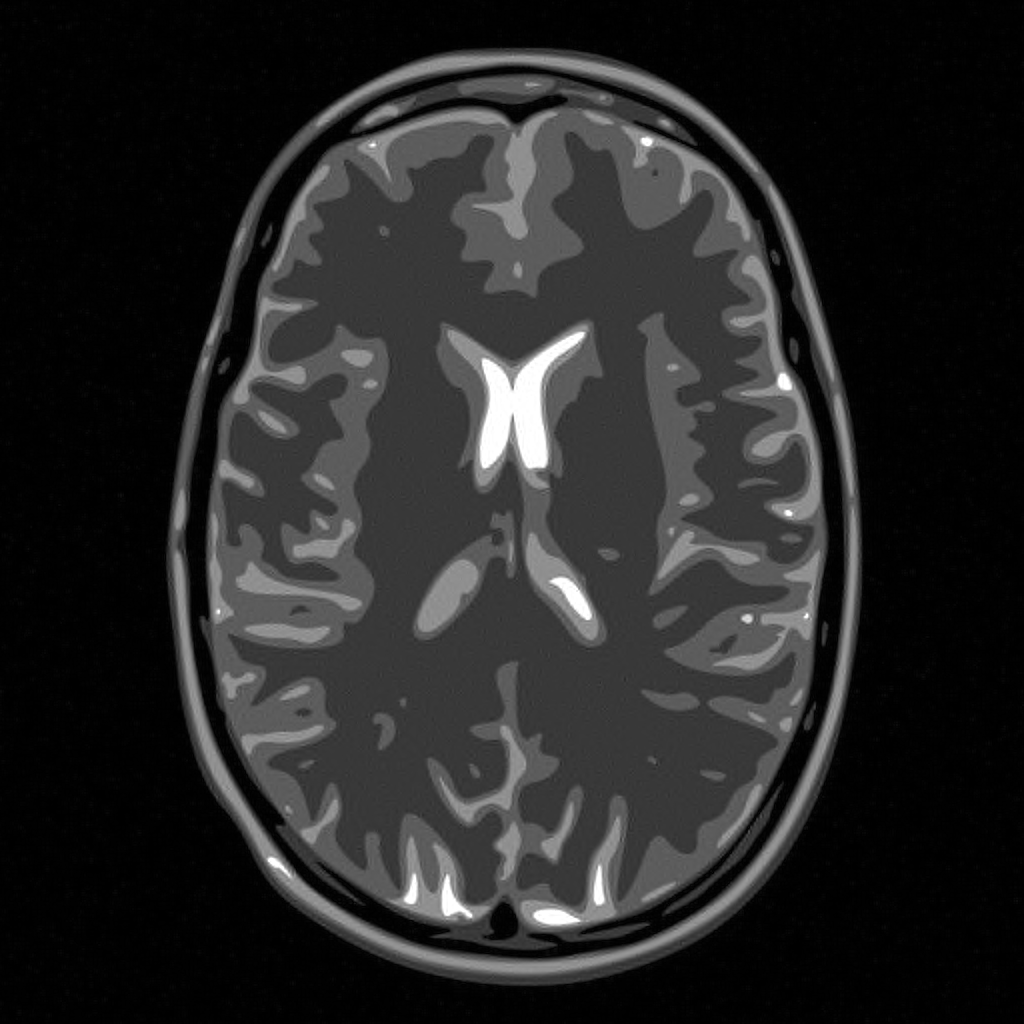

To test the practicality of the incoherence condition, let us consider a typical CS problem. In a number of important applications, not least MRI, the sampling is carried out in the Fourier domain. Since images are sparse in wavelets, the usual CS setup is to form the a matrix , where and represent the discrete Fourier and wavelet transforms respectively. However, in the case the coherence satisfies as , for any wavelet basis. Thus, this problem has the worst possible coherence, and the standard CS estimate (2.2) states that samples are needed in this case (i.e. full sampling), even though the object to recover is typically highly sparse. Note that this is not an insufficiency of the theory. If uniform random subsampling is employed, then the lack of incoherence does indeed lead to a very poor reconstruction. This can be seen in Figure 1.

In view of this, one may wonder how it is possible that CS is applied so successfully to many such problems. The key is so-called asymptotic incoherence (see §3.1) and the use of a variable density/multilevel subsampling strategy. The success of such subsampling is confirmed numerically in Figure 1. However, it is important to note that this is an empirical solution to the problem. None of the usual theory explains the effectiveness of CS when implemented in this way.